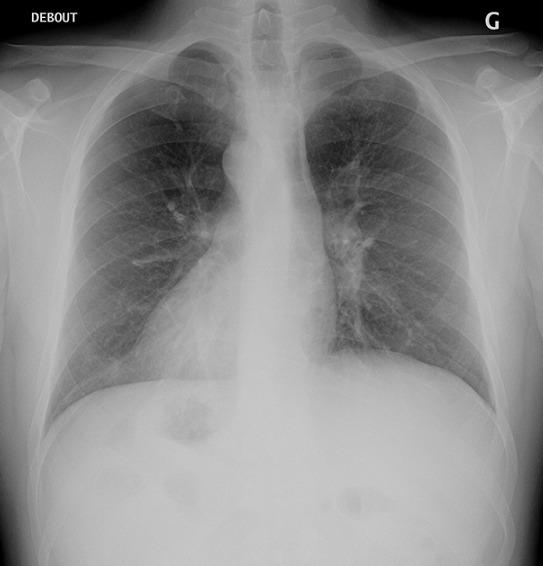

Kartagener's syndrome is a rare primitive ciliary dyskinesia (DCP) characterized by a clinical triad: sinusitis, bronchiectasis and complete or incomplete situs inversus. It is a rare congenital autosomal recessive disease. We report a case of Kartagener syndrome in an infertile couple with akinospermia detected using spermogram.